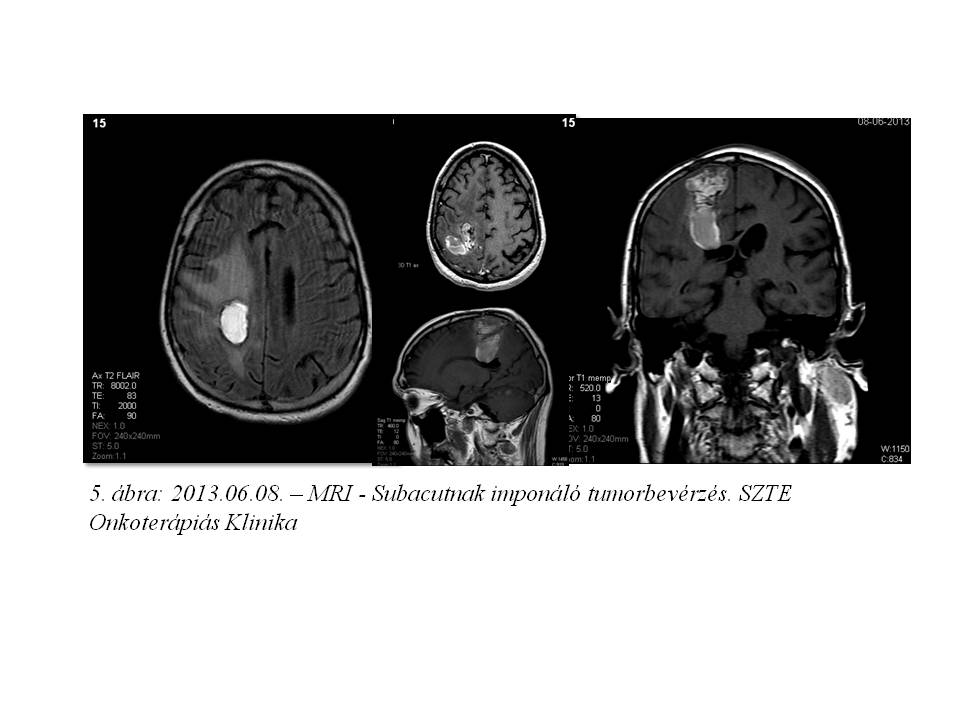

A 39 éves férfi betegnél 2004 nyarán jobb oldali parieto-occipitalis térfoglaló folyamatot detektáltak CT vizsgálattal, mely 2008 augusztusában növekedni kezdett (1. ábra). Az elvégzett biopszia grade II oligodendrogliomát igazolt. A beteg ezt követően definitív dózisú (22x1,8 Gy + 12x1,8 Gy) irradiációban részesült (2. ábra). 2 éven át fokozatos tumor regressziót, és stabil betegséget észleltünk, majd klinikailag stabil állapota mellett készült MR képalkotás 2010 júniusában tumor progressziót mutatott (3. ábra). Ekkor funkcionális MR és diffúzió súlyozott tractographia alapján neuronavigációs éber műtét során a makroszkópos tumor eltávolítása megtörtént. A hisztopatológia ekkor anaplasticus irányba transzformálódó, grade II-III oligodendrogliomát írt le. Posztoperatív 20x1,6 Gy dózisú reirradiáció történt, majd temozolomide monoterápia indult, mely 23 cikluson keresztül folytatódott (4. ábra). Ismételt tumor progresszió miatt 2012 szeptemberében betegünk reoperáción esett át, recidiváló, grade III-IV malignusan transzformálódó oligodendroglioma diagnózisával. A mozgásrehabilitáció mellett bevacizumab monoterápia indult egyedi méltányossággal, melyet 2013 júliusában kontroll MR által leírt subacut bevérzés miatt 4 ciklust követően a beteg kérésére felfüggesztettünk (5. ábra), 10 hónap viszonylagos jó állapot után gyors progresszió, majd 2014.06.27-én exitus következett be.